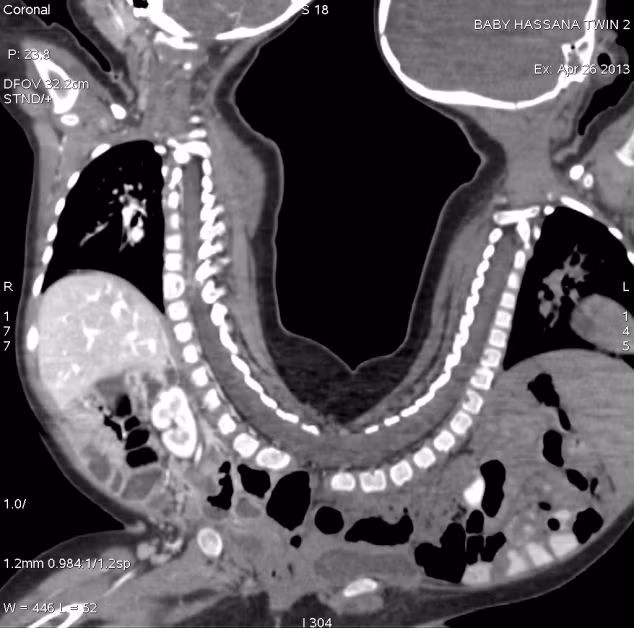

Hình ảnh minh họa cặp song sinh dính liền có chung phần xương sống. Tiến sĩ Prashant Jain, trưởng nhóm phẫu thuật cho biết ca phẫu thuật tách rời này là một thách thức lớn với các bác sĩ bởi 2 bé này có chung những bộ phần bất thường như ống tiêu hóa, hệ thống sinh dục và thần kinh.